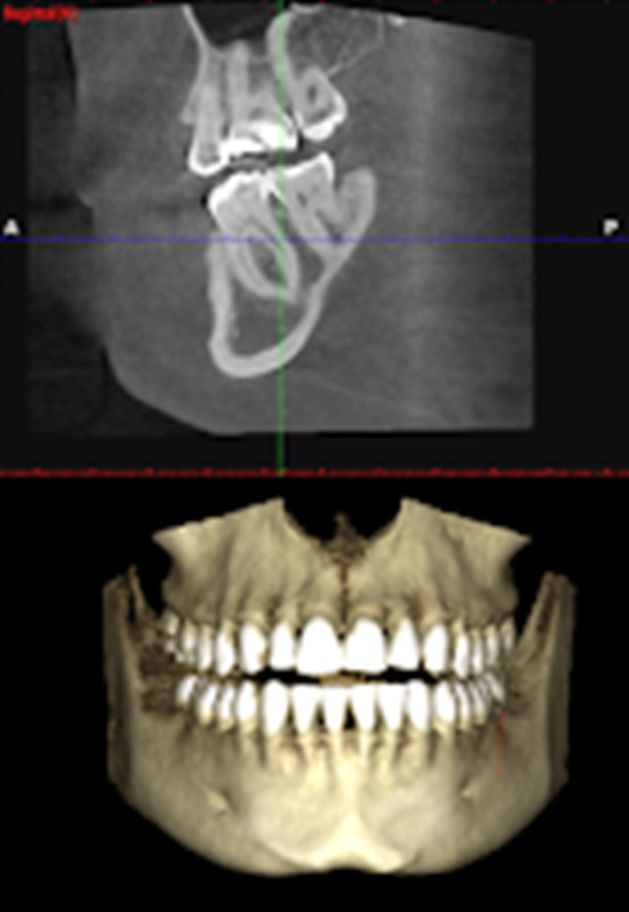

ΑΞΟΝΙΚΗ ΤΟΜΟΓΡΑΦΙΑ ΚΩΝΙΚΗΣ ΔΕΣΜΗΣ (CBCT)

Αποτελεί πλέον σημαντική διαγνωστική μέθοδο στην οδοντιατρική γιατί προσφέρει αναλυτικές πληροφορίες για την κατάσταση των οστών και την έκταση μιας βλάβης. Πλεονεκτεί σημαντικά της πανοραμικής ακτινογραφίας λόγω της τρισδιάστατης ανακατασκευής των εικόνων. Βοηθά σημαντικά στη μελέτη οστικών αλλοιώσεων (καλοήθους ή κακοήθους αιτιολογίας) αλλά και στην πρώιμη διάγνωση της οστεοπόρωσης.

Στις περιπτώσεις τοποθέτησης εμφυτευμάτων έχει καθοριστικό ρόλο στη σωστότερη και ακριβέστερη εμφύτευση καθώς και στην επιλογή των καταλληλότερων υλικών. Υπερτερεί σε μεγάλο βαθμό της συμβατικής αξονικής τομογραφίας (CT) λόγω των μικρότερων δόσεων απορροφούμενης ακτινοβολίας, του χαμηλότερου κόστους αλλά και της ταχύτερης και φιλικότερης εξέτασης.

Επισημαίνεται ότι ο ασθενής εξετάζεται σε όρθια θέση, όπως σε μια απλή πανοραμική ακτινογραφία και δεν υποβάλλεται στη σχετική "ταλαιπωρία" της κλασσικής, σε ύπτια θέση, αξονικής τομογραφίας.